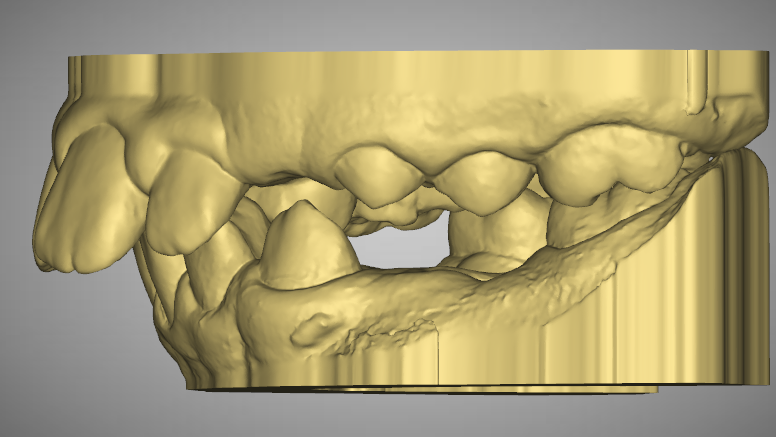

Pre-Op Analysis – 2020-11-25

- Class 2 div I and div II

- Mixed Dentition

STAGE 1

- RETRACT UPPER ANTERIORS AND CLOSE UPPER DIASTEMA TO HELP RELEASE LOWER LIP ENTRAPMENT

- Yellow Stone Model = Pre-Op at 2020

- Blue Overlay = Progress scan at 2022-07-04 after about 12 months of Mybrace K1 which came after 6 months in aligners.